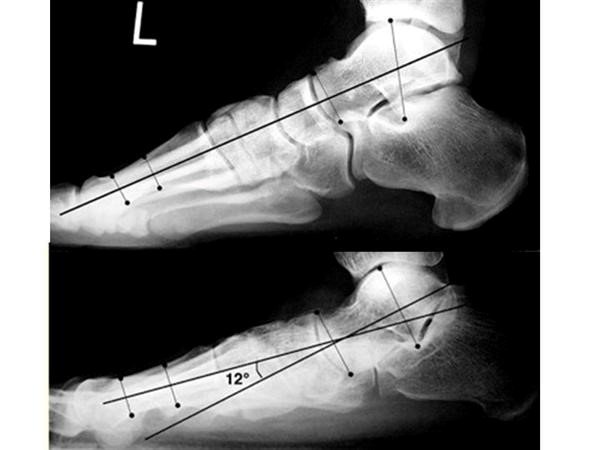

Chẩn đoán hình ảnh dóng vai trò rất lớn trong việc đánh giá cấu trúc xương của trẻ. Đầu tiên là phim Xquang bàn chân, cổ chân thẳng, nghiêng ở tư thế đứng sẽ giúp cung cấp những thông tin giá trị về những bất thường về giải phẫu các xương bàn chân, bất thường về khớp cổ chân cũng như giúp đo giá trị các góc giải phẫu quan trọng. Ví dụ với bàn chân bẹt thì góc Meary (ở hình dưới) sẽ lớn hơn 4 độ.